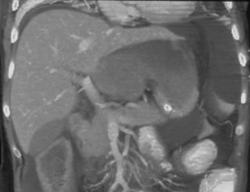

Diagnosis

Hemorrhagic Gastritis